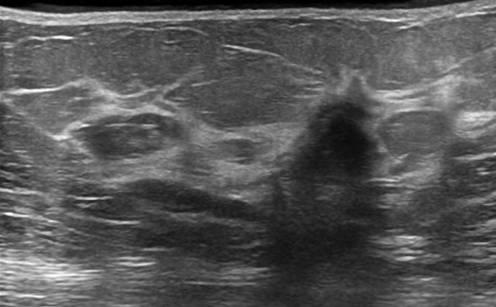

Ung thư vú

Ung thư vú - Ảnh 2

Ung thư vú - Ảnh 3

» Thông tin: Nữ giới – 50 tuổi.

» Lâm sàng: Khối tuyến vú.